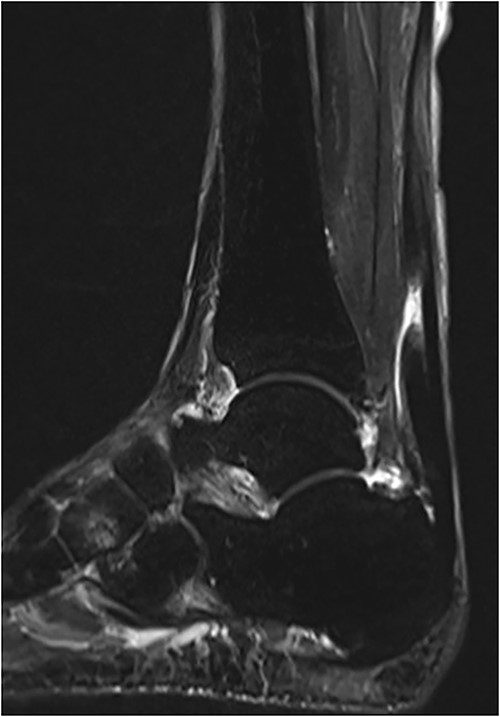

The operation was performed under general anesthesia in the prone position with an air tourniquet. First, a 6 cm longitudinal incision was made along the mid-medial aspect of the Achilles tendon to identify the rupture site. Scar tissue and degenerated tendon were found at the rupture site and were adequately debrided. With the operated ankle in neutral position, the Achilles tendon gap was 2 cm. Using the modified SLLS technique introduced by Imade et al. [6], the ruptured tendon was directly sutured with USP 5 braided polyethylene and polyester suture thread (FiberWire; Arthrex Co., Naples, FL, USA). A 4-0 monofilament nylon thread was then used to create a peripheral cross-stitch suture (Fig. 2). Finally, the wound was stitched closed and the operation was completed.

(A) In the rupture site, scar tissues and degenerative tendon were seen. (B) After these tissues were adequately debrided, the ruptured tendon was directly repaired using the modified SLLS technique.